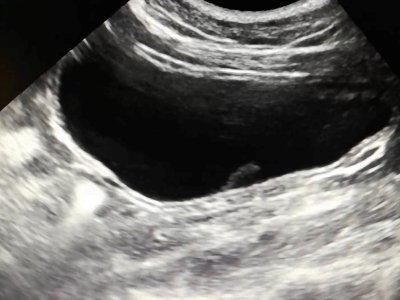

Koty cierpiące na idiopatyczne zapalenie pęcherza moczowego manifestują objawy kliniczne charakterystyczne dla wielu jednostek chorobowych dotyczących dolnych dróg moczowych, dlatego ostateczne rozpoznanie wymaga wnikliwej diagnostyki i wykluczenia istnienia innych chorób urologicznych. Diagnostyka ta obejmuje badanie ogólne moczu, posiew bakteriologiczny, badanie ultrasonograficzne oraz RTG układu moczowego, w pewnych przypadkach uzupełnione o kontrastowanie.